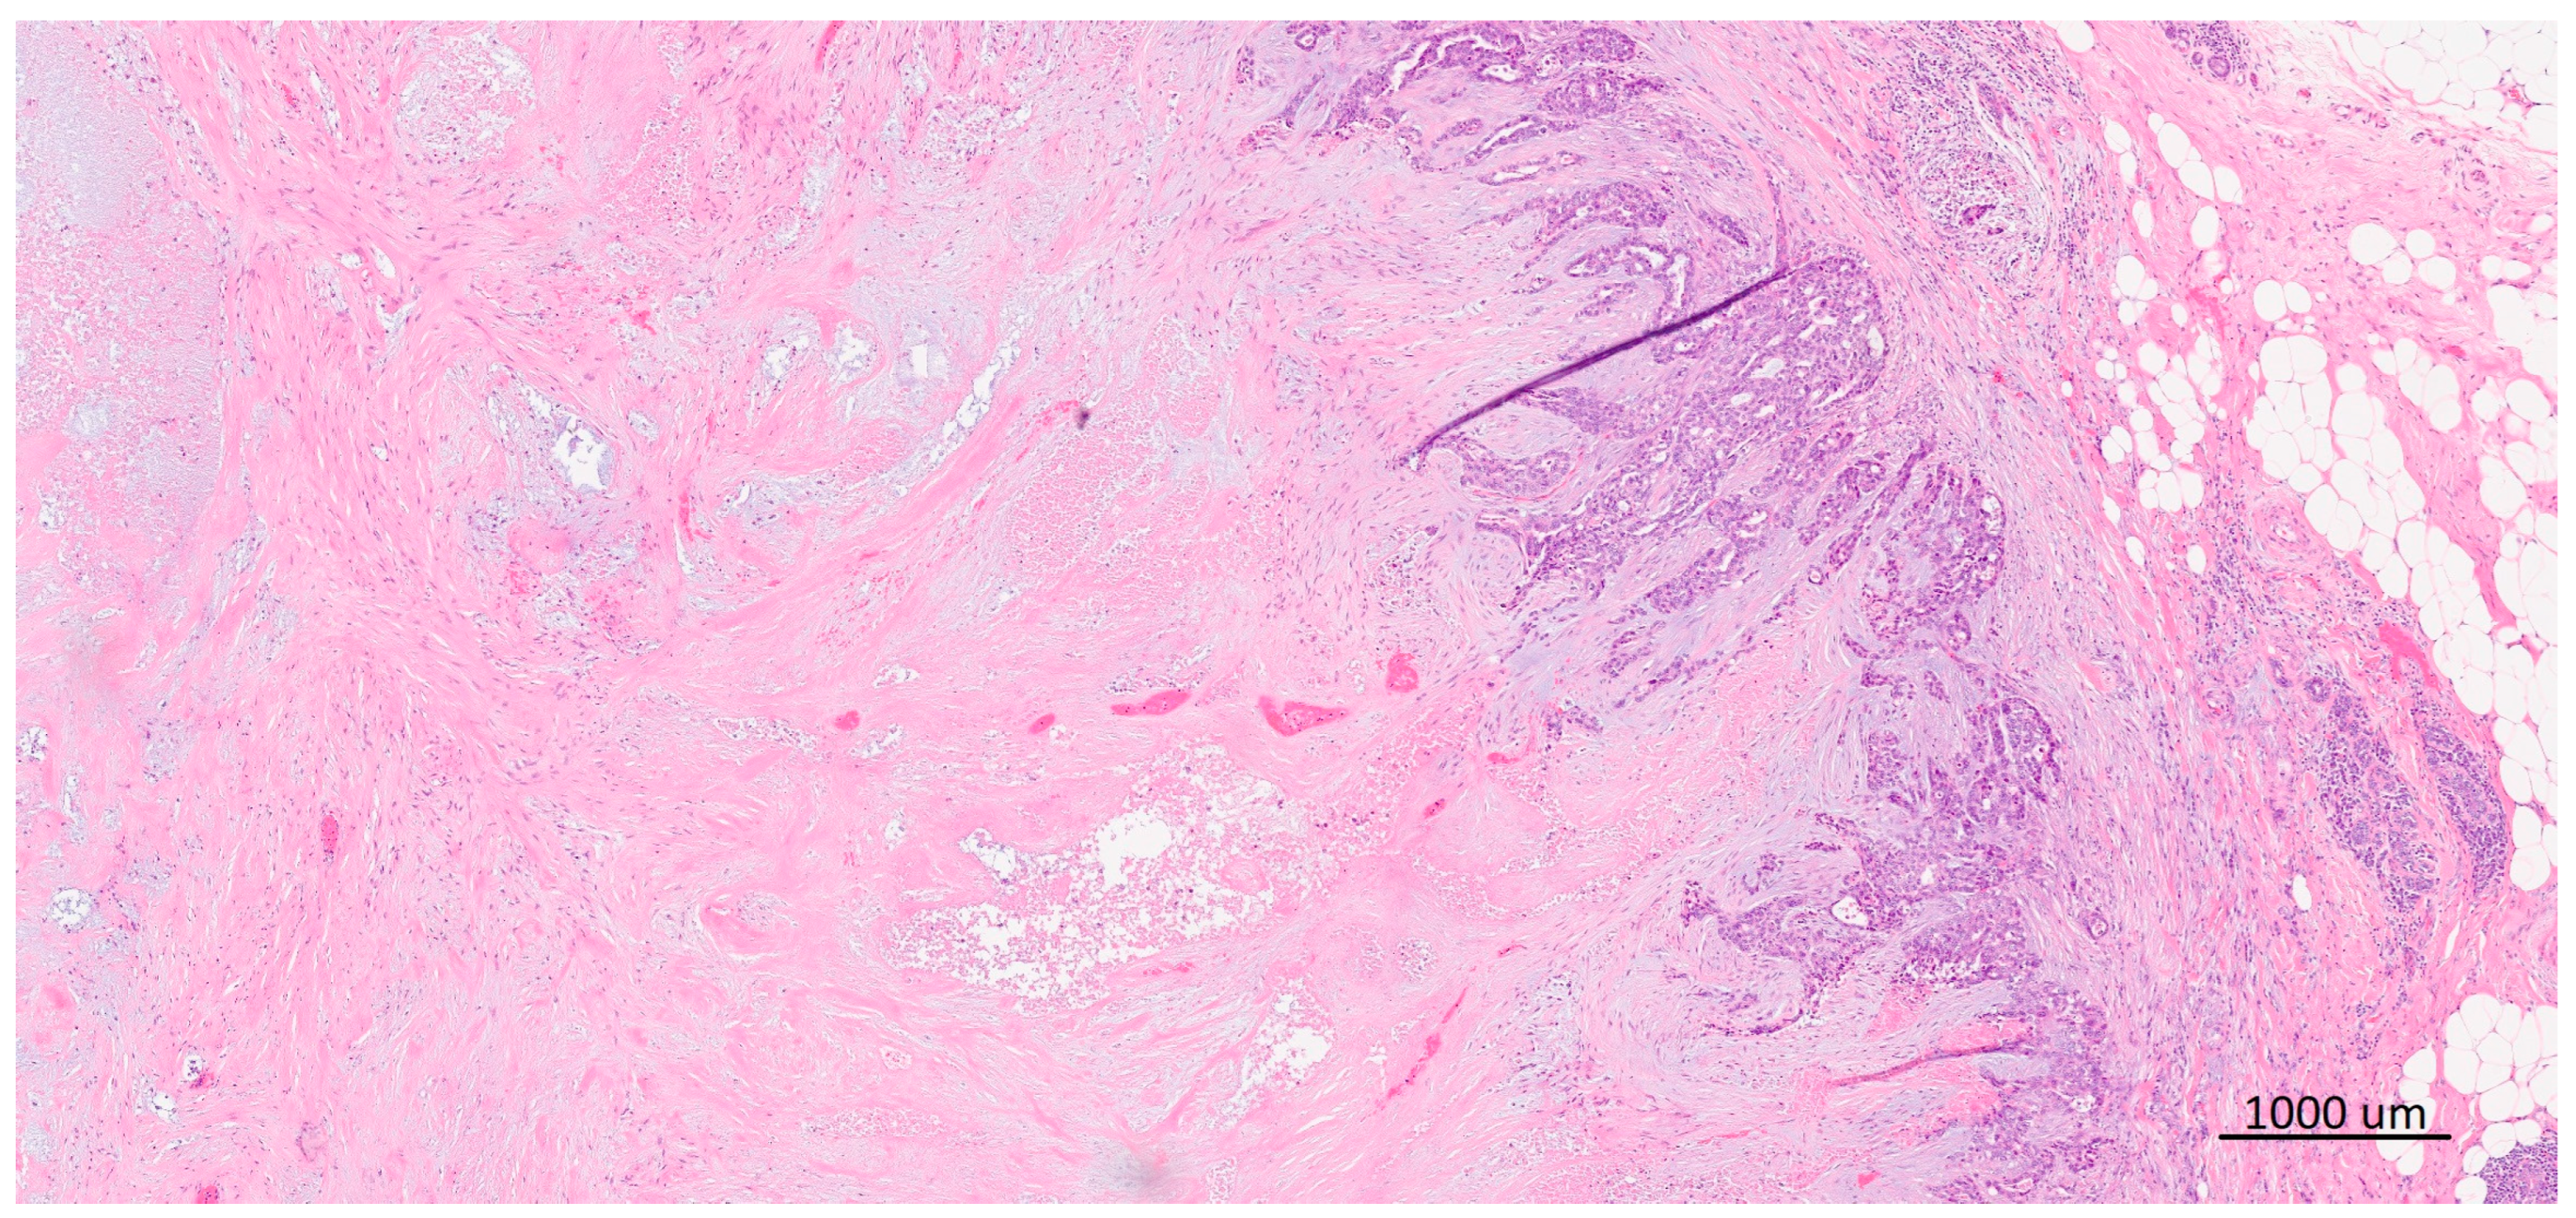

2.2. “Basal-like” Morphology